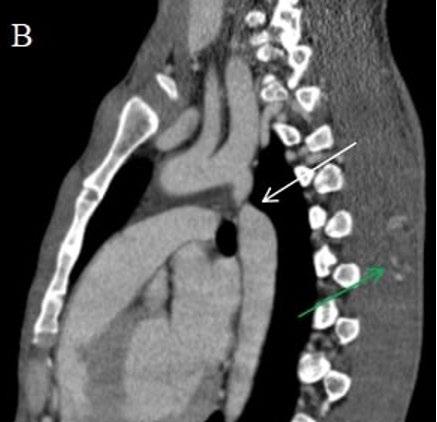

83 Coarctation of Aorta Masquerading as a Spinal Arteriovenous Malformation: A Case Report

Badhe et al.